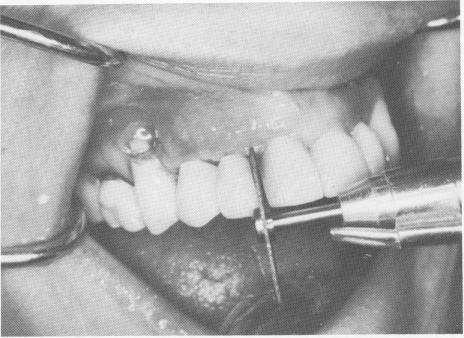

Fig. 7-94. A vent-plant being inserted in the right cuspid region.

4 Vent-plant endosseous implant inserted in right cuspid region